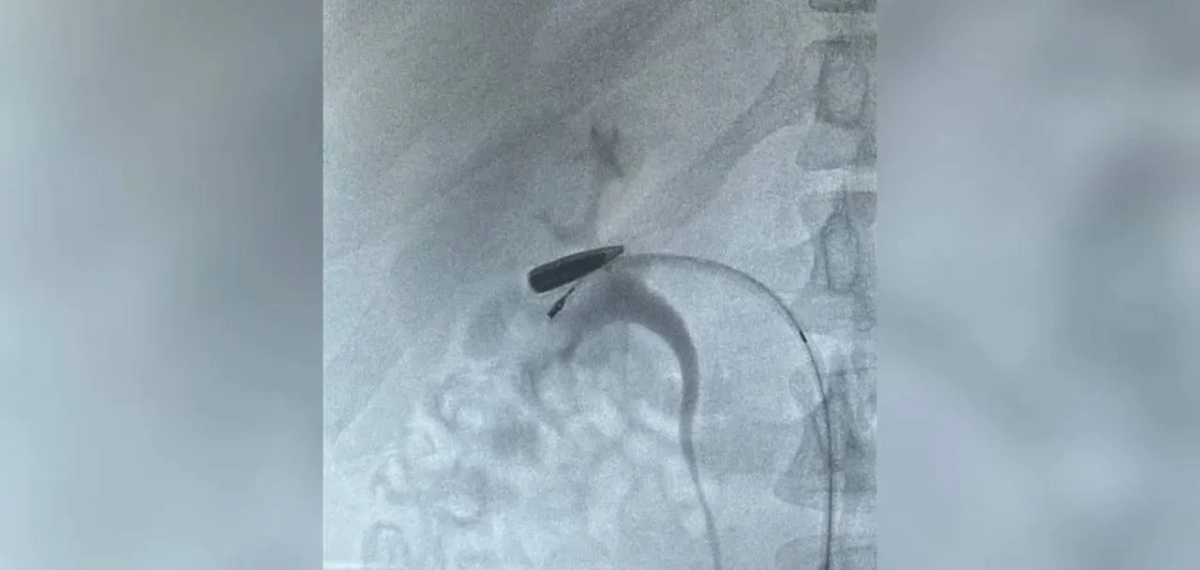

Из Курской области в Москву вертолётом эвакуировали мужчину с редким ранением: пуля калибра 5,45 мм, пройдя по венам от ключицы до области почки, остановилась в считанных миллиметрах от органа. Об этом сообщили в телеграм-канале Московская медицина.

«На КТ было обнаружено, что пуля мигрировала по верхней и нижней полым венам от места ранения и остановилась в правой почечной вене. Такой путь инородного тела — редчайший случай», — говорится в сообщении.

Хирурги института Склифосовского оперативно направили пациента в ангиографическую гибридную операцию, в ходе которой смогли извлечь пулю и восстановили кровоток. По словам медиков, мужчину удалось спасти, почка при этом не пострадала. Сейчас раненый находится в создании, его состояние оценивают как стабильное.